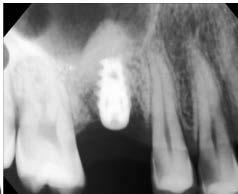

40 años acudió para la rehabilitación del sector posterior superior, pues presentaba un defecto vertical en el cuadrante superior derecho a la altura del primer molar, una altura óseorresidual de 3.5 mm y un tipo óseo III. Dadas las condiciones, se optó por la técnica de oseodensificación para la elevación del piso del seno maxilar y la preparación del lecho implantario. Entre los hallazgos descritos en los resultados se encontró una elevación sinusal de al menos 6 mm, evidenciada en las imágenes radiográficas intraoperartorias, que permitió la colocación de un implante de 5 mm de plataforma por 8 mm de longitud, ubicado 1 mm en posición subcrestal. Una tomografía

axial computarizada confirmó la situación del implante, así como la efectividad de la oseodensificación y la elevación del piso sinusal de 6 mm. la osteointegración del implante se completó sin necesidad de procedimientos quirúrgicos adicionales de mayor complejidad. Se concluye que la oseodensificación es una técnica eficaz y predecible para la osteotomía y la elevación sinusal transcrestal, favorece la estabilidad primaria del implante y constituye un procedimiento mínimamente invasivo.

Figura 2. Planeación en tomografía axial computarizada: a) vista sagital, b) vista transversal, c) vista 360°, d) reconstrucción 3D y e) ortopantomografía.

quirúrgico de elevación sinusal transcrestal y osteotomía, para optimizar la estabilidad primaria y la integración ósea en la colocación de implantes dentales endoóseos, mediante medición del torque de inserción y comprobación radiográfica que muestre la elevación sinusal y el implante colocado en el sitio requerido. Rehabilitar la zona edéntula de la paciente para restaurar la función estética y masticatoria sin recurrir a procedimientos quirúrgicos invasivos.

Figura 3. Protocolo de fresado quirúrgico: a) fresa piloto sentido horario, b) comprobación radiográfica, c) RX pin de paralelismo, d) fresa 2.3 sentido antihorario, e) comprobación radiografía periapical de posición y elevación del piso de seno, f) fresa 3.2 a 9mm con elevación evidente, g) verificación de profundidad con sonda del kit de implantes, h) colocación de injerto de hueso NovaBone, i) vista del hueso en el lecho quirúrgico j) fresa final diámetro 4.3, k) RX de comprobación de fresa 4.3 y l) RX de implante e injerto colocados.

fresado (fresa de 4.2 mm de diámetro) dentro del sitio preparado como indica el protocolo de fresado Versah. Gracias al diseño específico de las fresas, el biomaterial fue distribuido hacia las zonas superior y lateral del sitio quirúrgico para promover una adecuada condensación ósea y facilitar la colocación del implante en una posición subcrestal de 1 mm.

Entre cada cambio de fresa, se verificó radiográficamente la dirección y profundidad del fresado. Finalmente, se completó el protocolo con el uso de la fresa de 4.2 mm de diámetro hasta alcanzar una profundidad final de 9 mm. Se obtuvieron imágenes radiográficas que evidencian la correcta colocación del injerto en la elevación lograda (ver Figura 3).

Figura 4. Comprobación de estabilidad inicial mediante torque de inserción: a) llave dinamométrica inserta el implante a su sitio final y b) acercamiento muestra torque de inserción de 100 N·cm.

alguna. 3 meses después se valoró con ortopantomografía (Figura 5).

Resultados

Se logró una elevación sinusal de 6 mm en el sitio destinado para la colocación del implante endoóseo. Se colocó injerto sintético en la zona elevada para implantar en una única sesión quirúrgica, y se obtuvo un torque final de 100 N•cm, lo que indicó una excelente estabilidad primaria. La rehabilitación protésica se realizó sin complicación alguna, mediante una corona atornillada metal-cerámica, 2 meses después de haber colocado el implante. La integridad de la restauración se mantuvo en óptimas condiciones durante el seguimiento clínico a 5 años de la rehabilitación.

Figura 5. Ortopantomografía 3 meses después de colocado el implante. Se aprecia la elevación sinusal y el hueso injertado.